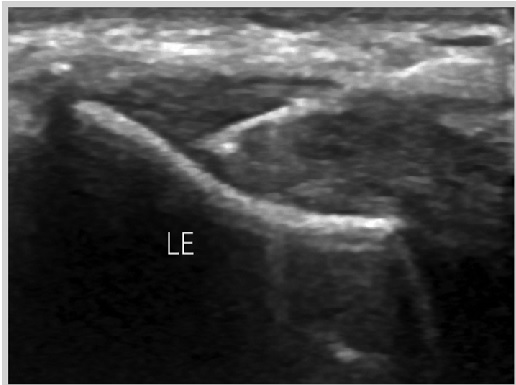

Ultraljudsvägledd Epte - Electrolysis percutaneous therapy

Epte är en mycket bra och specifik behandlingsmetod för behandling av tendinopatier, alltså problem i från senor och muskler efter överbelastningar. De problem som kan behandlas med Epte är hopparknä (smärta vid knäskålen), tennisarmbåge, golfarmbåge supraspinatussena och infraspinatussena i axeln, hälsena, hälsporre (plantar fasciit). Epte används på både idrottsaktiva och mindre aktiva.

Med hjälp av den lokala strömmen framkallas en lokal kontrollerad inflammation för att få till en läkning. Inflammation är den process man vill ha efter en överbelastning då det är den process som läker skadan. Vid problem i senor (tendinopatier) är det ofta är avsaknaden av inflammatorisk process eller en för liten inflammation som gör att det ofta inte läker som det ska och istället blir till en degenerativ process i senan.